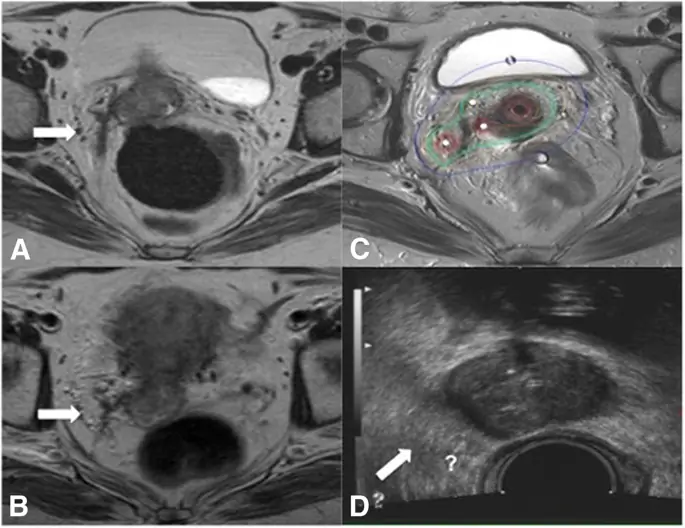

Еще одна причина может зависеть от формы и типа опухолевого роста. Очень прогрессирующие стадии опухоли (FIGO IVA) показывают более вероятный инфильтративный рост с неправильными формами и тонкими оцифровками, которые глубоко проникают в параметрическое пространство по сравнению с объемными экспансивными опухолями шейки матки, которые обычно более отчетливо видны при визуализации TRUS (фиг. 2 и 3).

Случай рака шейки матки FIGO стадии IIIB с ограниченным ответом на EBRT с плохим согласием между pre BT MR и preBT TRUS в измерениях опухоли. Опухоль во время диагностической МР (а), во время МРТ до бТ (б) и во время первой БТ (в). В preBT TRUS (d) правильное параметрическое вторжение (белые стрелки) не так отчетливо видно, как в MR (a - b - c)

Изображение в полном размере